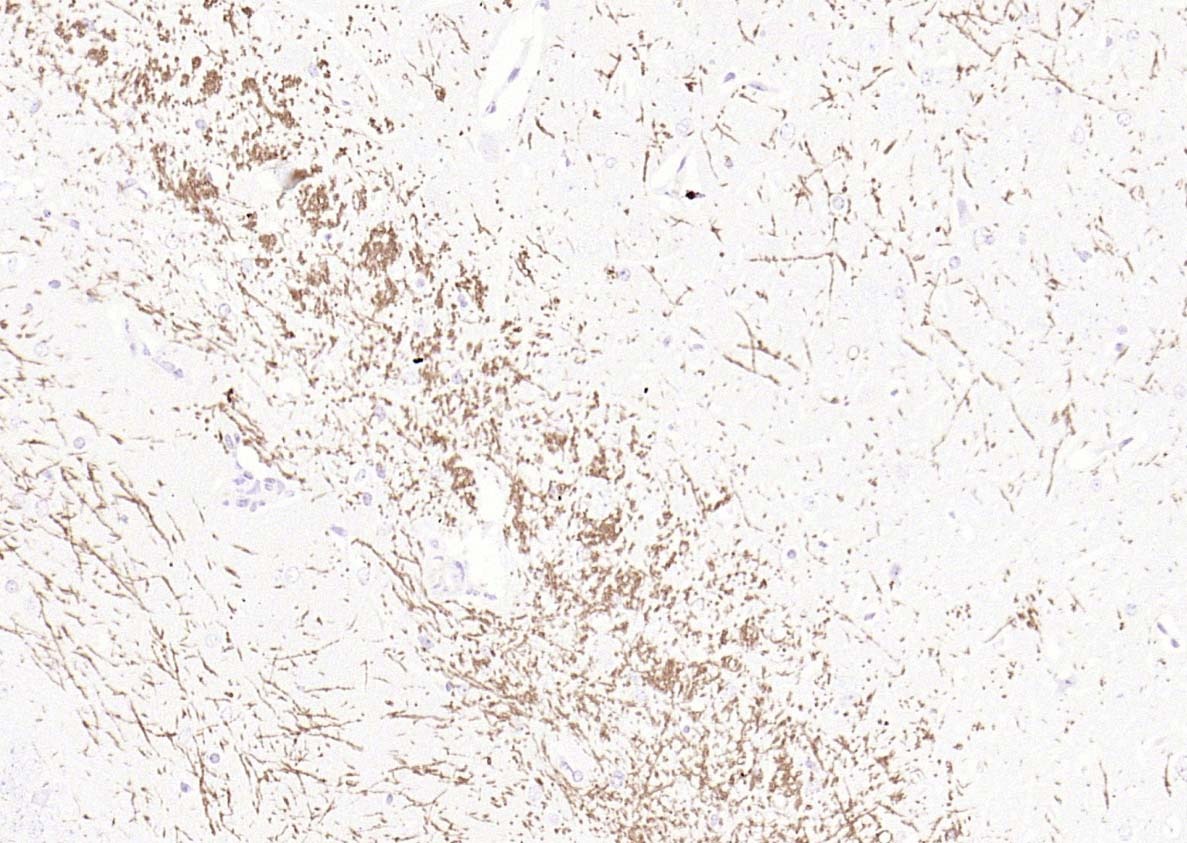

4. Paraformaldehyde-fixed, paraffin embedded (rat brain); Antigen retrieval by boiling in sodium citrate buffer (pH6.0) for 15 min; Block endogenous peroxidase by 3% hydrogen peroxide for 20 min; Blocking buffer (normal goat serum) at 37°C for 30 min; Antibody incubation with (MBP) Polyclonal Antibody, Unconjugated (TMAB-01110) at 1:200 overnight at 4°C, followed by operating according to SP Kit (Rabbit) instructionsand DAB staining.

5. Paraformaldehyde-fixed, paraffin embedded (mouse brain); Antigen retrieval by boiling in sodium citrate buffer (pH6.0) for 15 min; Block endogenous peroxidase by 3% hydrogen peroxide for 20 min; Blocking buffer (normal goat serum) at 37°C for 30 min; Antibody incubation with (MBP) Polyclonal Antibody, Unconjugated (TMAB-01110) at 1:200 overnight at 4°C, followed by operating according to SP Kit (Rabbit) instructionsand DAB staining.

11. Paraformaldehyde-fixed, paraffin embedded Mouse Cerebellum; Antigen retrieval by boiling in sodium citrate buffer (pH6.0) for 15 min; The section was incubated with MBP Polyclonal Antibody, Unconjugated (TMAB-01110) at 1:1500 overnight at 4°C, followed by conjugation to the secondary antibody and DAB staining.

12. Paraformaldehyde-fixed, paraffin embedded Rat Cerebellum; Antigen retrieval by boiling in sodium citrate buffer (pH6.0) for 15 min; The section was incubated with MBP Polyclonal Antibody, Unconjugated (TMAB-01110) at 1:1500 overnight at 4°C, followed by conjugation to the secondary antibody and DAB staining.

13. Paraformaldehyde-fixed, paraffin embedded Human Cerebellum; Antigen retrieval by boiling in sodium citrate buffer (pH6.0) for 15 min; The section was incubated with MBP Polyclonal Antibody, Unconjugated (TMAB-01110) at 1:1500 overnight at 4°C, followed by conjugation to the secondary antibody and DAB staining.

14. Paraformaldehyde-fixed, paraffin embedded Human Cerebrum; Antigen retrieval by boiling in sodium citrate buffer (pH6.0) for 15 min; The section was incubated with MBP Polyclonal Antibody, Unconjugated (TMAB-01110) at 1:1500 overnight at 4°C, followed by conjugation to the secondary antibody and DAB staining.